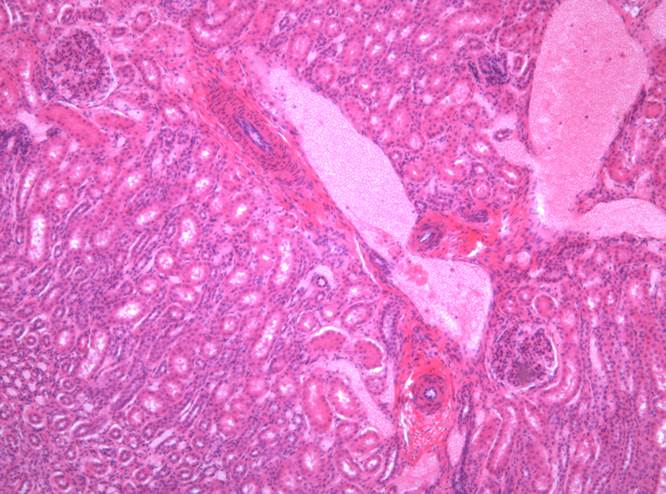

Препарат № 1. «Почка взрослого»,(окраска гематоксилином и

ОГП - 126 эозином).

- Корковое вещество:

3. почечное тельце;

4. сосудистый клубочек;

5. наружный листок капсулы почечного тельца;

6. полость почечного тельца;

7. проксимальный извитой каналец;

8. дистальный извитой каналец.

9. собирательная трубка

III. Мозговое вещество:

10. нисходящая часть тонкого канальца;

11. восходящая часть тонкого канальца;

12. петля (Генле),

13. собирательная трубка.